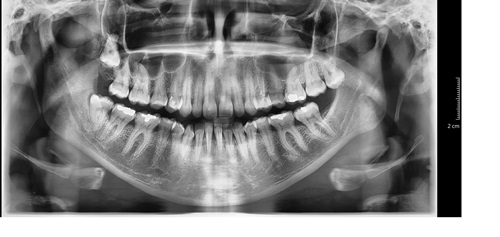

Imagem de um raio-X panorâmico digital, feito a partir do novo equipamento.

A Comissão de Saúde Bucal do Grupo Hospitalar Conceição (GHC) recebeu, em prol das melhorias tecnológicas para o atendimento no Sistema Único de Saúde (SUS), o novo aparelho de radiografia para exames com imagens digitalizadas. A ferramenta foi entregue às equipes de odontologia neste mês de abril.

A obtenção do novo raio-X foi definida como prioridade para o setor em reunião ocorrida em setembro do ano passado, junto à Diretoria Técnica do GHC. Com os exames digitalizados, as imagens terão mais qualidade e poderão ser acessadas pelos profissionais por meio do prontuário eletrônico.

A coordenadora do Centro de Especialidades Odontológicas (CEO/GHC), Ana Paula Braun, explica que, além da melhor qualidade das imagens e dos profissionais terem a facilidade de acessá-las pelo sistema integrado, “a rapidez com que o exame será entregue ao paciente irá melhorar o fluxo da rede de atenção, já que os pacientes esperarão menos tempo pelo exame e, consequentemente, para fazerem as consultas”.

O raio-X panorâmico digital também facilitará as rotinas de trabalho, uma vez que não será mais necessário o processo químico de revelação dos filmes. Além de beneficiar profissionais e usuários, diminui custos e não gera resíduos ao meio ambiente.